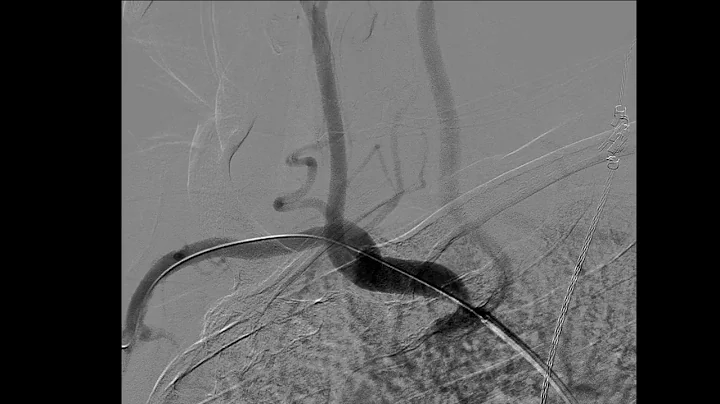

Dr. Ramzan Zakir, Subclavian And Brachiocephalic Stenting: Indications And Techniques